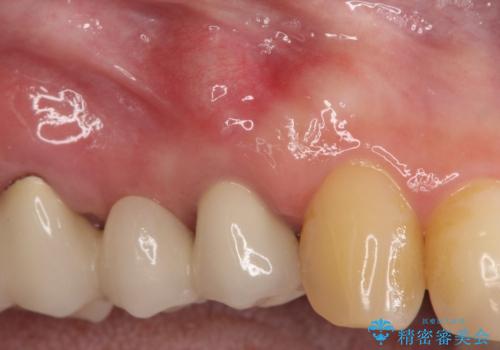

- 前医にて根っこの治療をしたが、歯肉が腫れてきたことを主訴に紹介された患者様です。

歯肉を押すと痛みがあり、レントゲンの画像でも病変があることがわかります。

6ヶ月経過し、症状もなくなり、病変も縮小していることが確認できます。